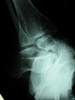

APR Fractura bimaleolar de tobillo